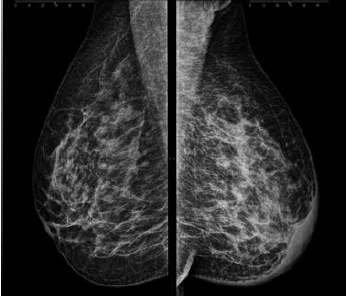

Uma paciente de 46 anos realizou esta mamografia.

Assinale a alternativa que contém a descrição e a classificação BIRADS correspondente.